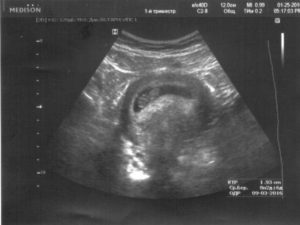

Однако женщина может и не чувствовать ничего подобного. В ряде случаев гипертонус матки при беременности определяется только на осмотре у гинеколога или на УЗИ.

Отдельно можно упомянуть о локальном гипертонусе матки по задней или передней стенке. Кстати, именно локализация может быть причиной того, что боль при гипертонусе ощущается женщиной только в каком-то одном месте: живот или поясница. На УЗИ гипертонус одной из стенок заметен по явной смене формы матки: одна из ее стенок прогибается вовнутрь.

Для уточнения диагноза беременная женщина должна протии обследование с помощью двуручного бимануального исследования.Для того чтобы уточнить диагноз, необходимо провести УЗИ либо инструментальное исследование. В первом триместре беременности гипертонус матки можно определить именно при проведении таких исследований. Особенно такое исследование будет продуктивным, в случае если гипертонус охватывает лишь переднюю или заднюю стенку матки.

В некоторых случая на первых неделях беременности гипертонус матки (как передней, так и задней стенки) может протекать бессимптомно и возникать как ответная реакция на проведение манипуляций (осмотра). Он диагностируется при ультразвуковом исследовании и проявляется в виде утолщения стенки матки.

Основным методом диагностики при появлении признаков гипертонуса передней стенки матки во время беременности является ультразвуковое исследование (УЗИ).

Во время процедуры УЗИ гипертонус матки выявить несложно: при наличии данного нарушения передняя стенка немного прогибается внутрь. Кроме того, эта сторона обычно более тонкая, чем задняя, поэтому установить диагноз специалисту не составит труда.